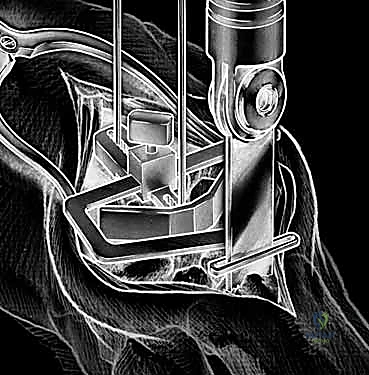

5. تجربة المفصل المؤقت

قبل تثبيت المفصل النهائي، يقوم الدكتور هطيف بوضع مفصل تجريبي للتأكد من المقاس الدقيق، واختبار نطاق الحركة، والتأكد من استقرار المفصل وتوازن الأربطة المحيطة به.

6. تثبيت المفصل الصناعي النهائي

يتكون المفصل الصناعي من جزأين رئيسيين: الجذع الكعبري (الذي يُزرع في عظمة الكعبرة في الساعد) والجذع الرسغي (الذي يُزرع في عظمة المشط الثالثة في اليد). يتم تثبيت هذه الأجزاء إما باستخدام الإسمنت العظمي الطبي، أو عن طريق الانحشار الميكانيكي الدقيق (Press-fit) الذي يسمح بنمو العظم داخل المفصل الصناعي. بين هذين الجزأين المعدنيين، توضع قطعة بلاستيكية عالية الجودة تعمل كغضروف صناعي يسمح بالحركة السلسة.